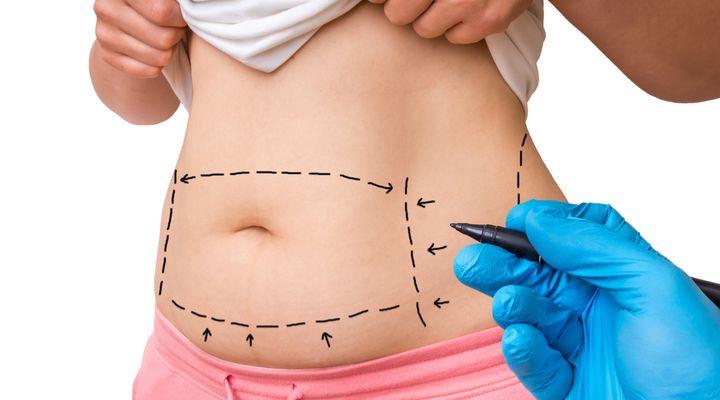

Tummy Tuck

Most liposuction procedures are followed by an abdominoplasty, otherwise known as a “tummy tuck.” Though this technique can make one look thinner and remove excess skin and fat, severe infections and clots can occur post-surgery.